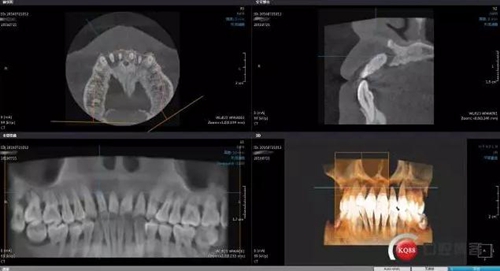

拔除上頜中切與側(cè)切牙同期GBR,手術(shù)中因?yàn)闆]有拍照片僅拍術(shù)后CBCT有些小遺憾

GBR術(shù)后CBCT